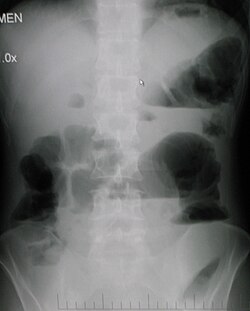

Bağırsaq keçməzliyi — bağırsaqların bu, yaxud digər səviyyəsində kənar edilə bilməyən maneə əmələ gələrək, onun içindəkilərin irəliləməsini pozaraq əmələ gəlir.